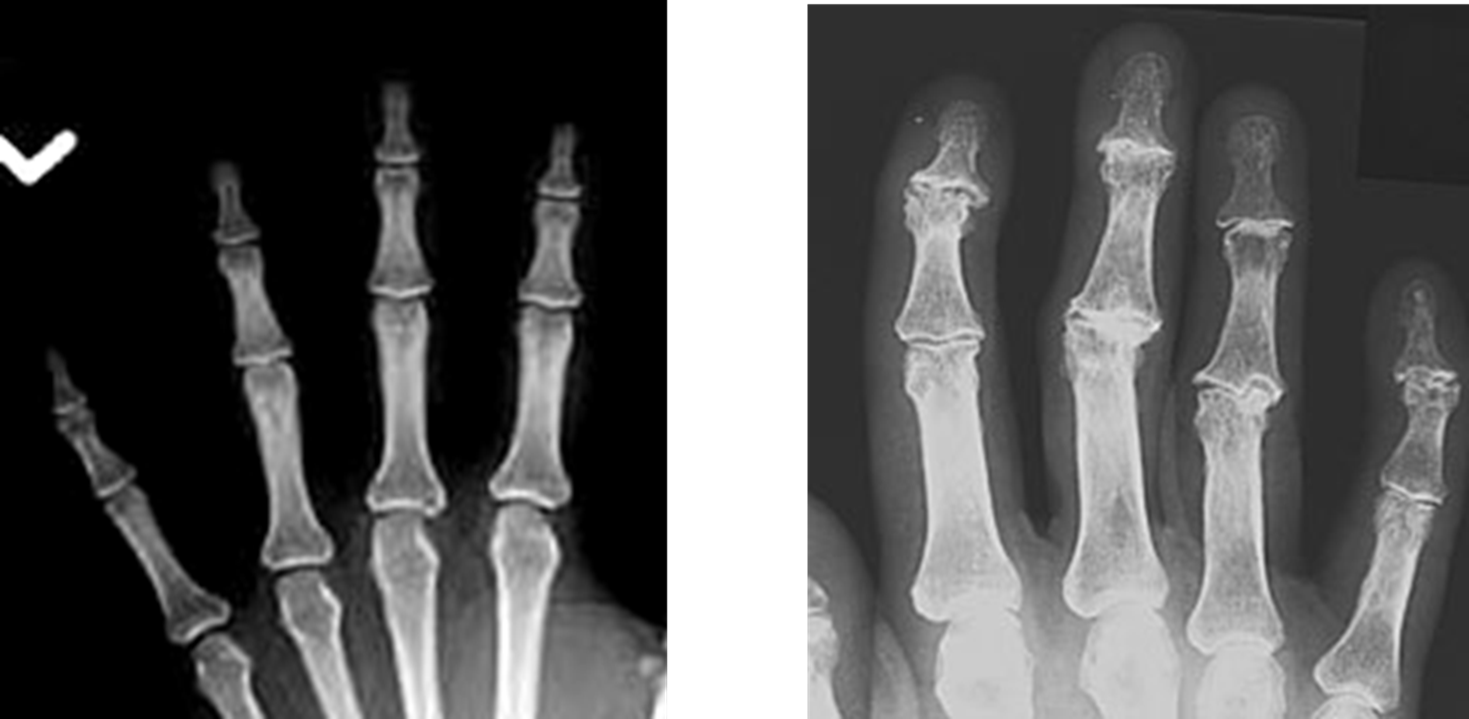

Osteoarthritis

(Degenerative Joint Disease)

Generalized disorder pathologically characterized by loss of joint cartilage and reactive new bone formation.

Cause: traumatic, stress to joints

Complications: joint pain, stiffness, trouble using joints for walking, grasping, etc

Radiographic Appearance: irregular narrowing of joint spaces and development of small bony spurs (osteophytes)

•Knee – articular ends become increasingly dense and joint narrowing is asymmetric

•Fingers – affect distal joints, marginal spurs produce well defined bony protuberances (can palpate and see knobby appearance)

•Hip – asymmetric narrowing of joint space (superiorly and laterally)

Technical: Advance Stage – Subtractive disease

•May require slight decrease

Prognosis: Some patients are unaffected by osteoarthritis while others can be severely disabled.

•Joint replacement surgery for some results in the best long-term outcome.